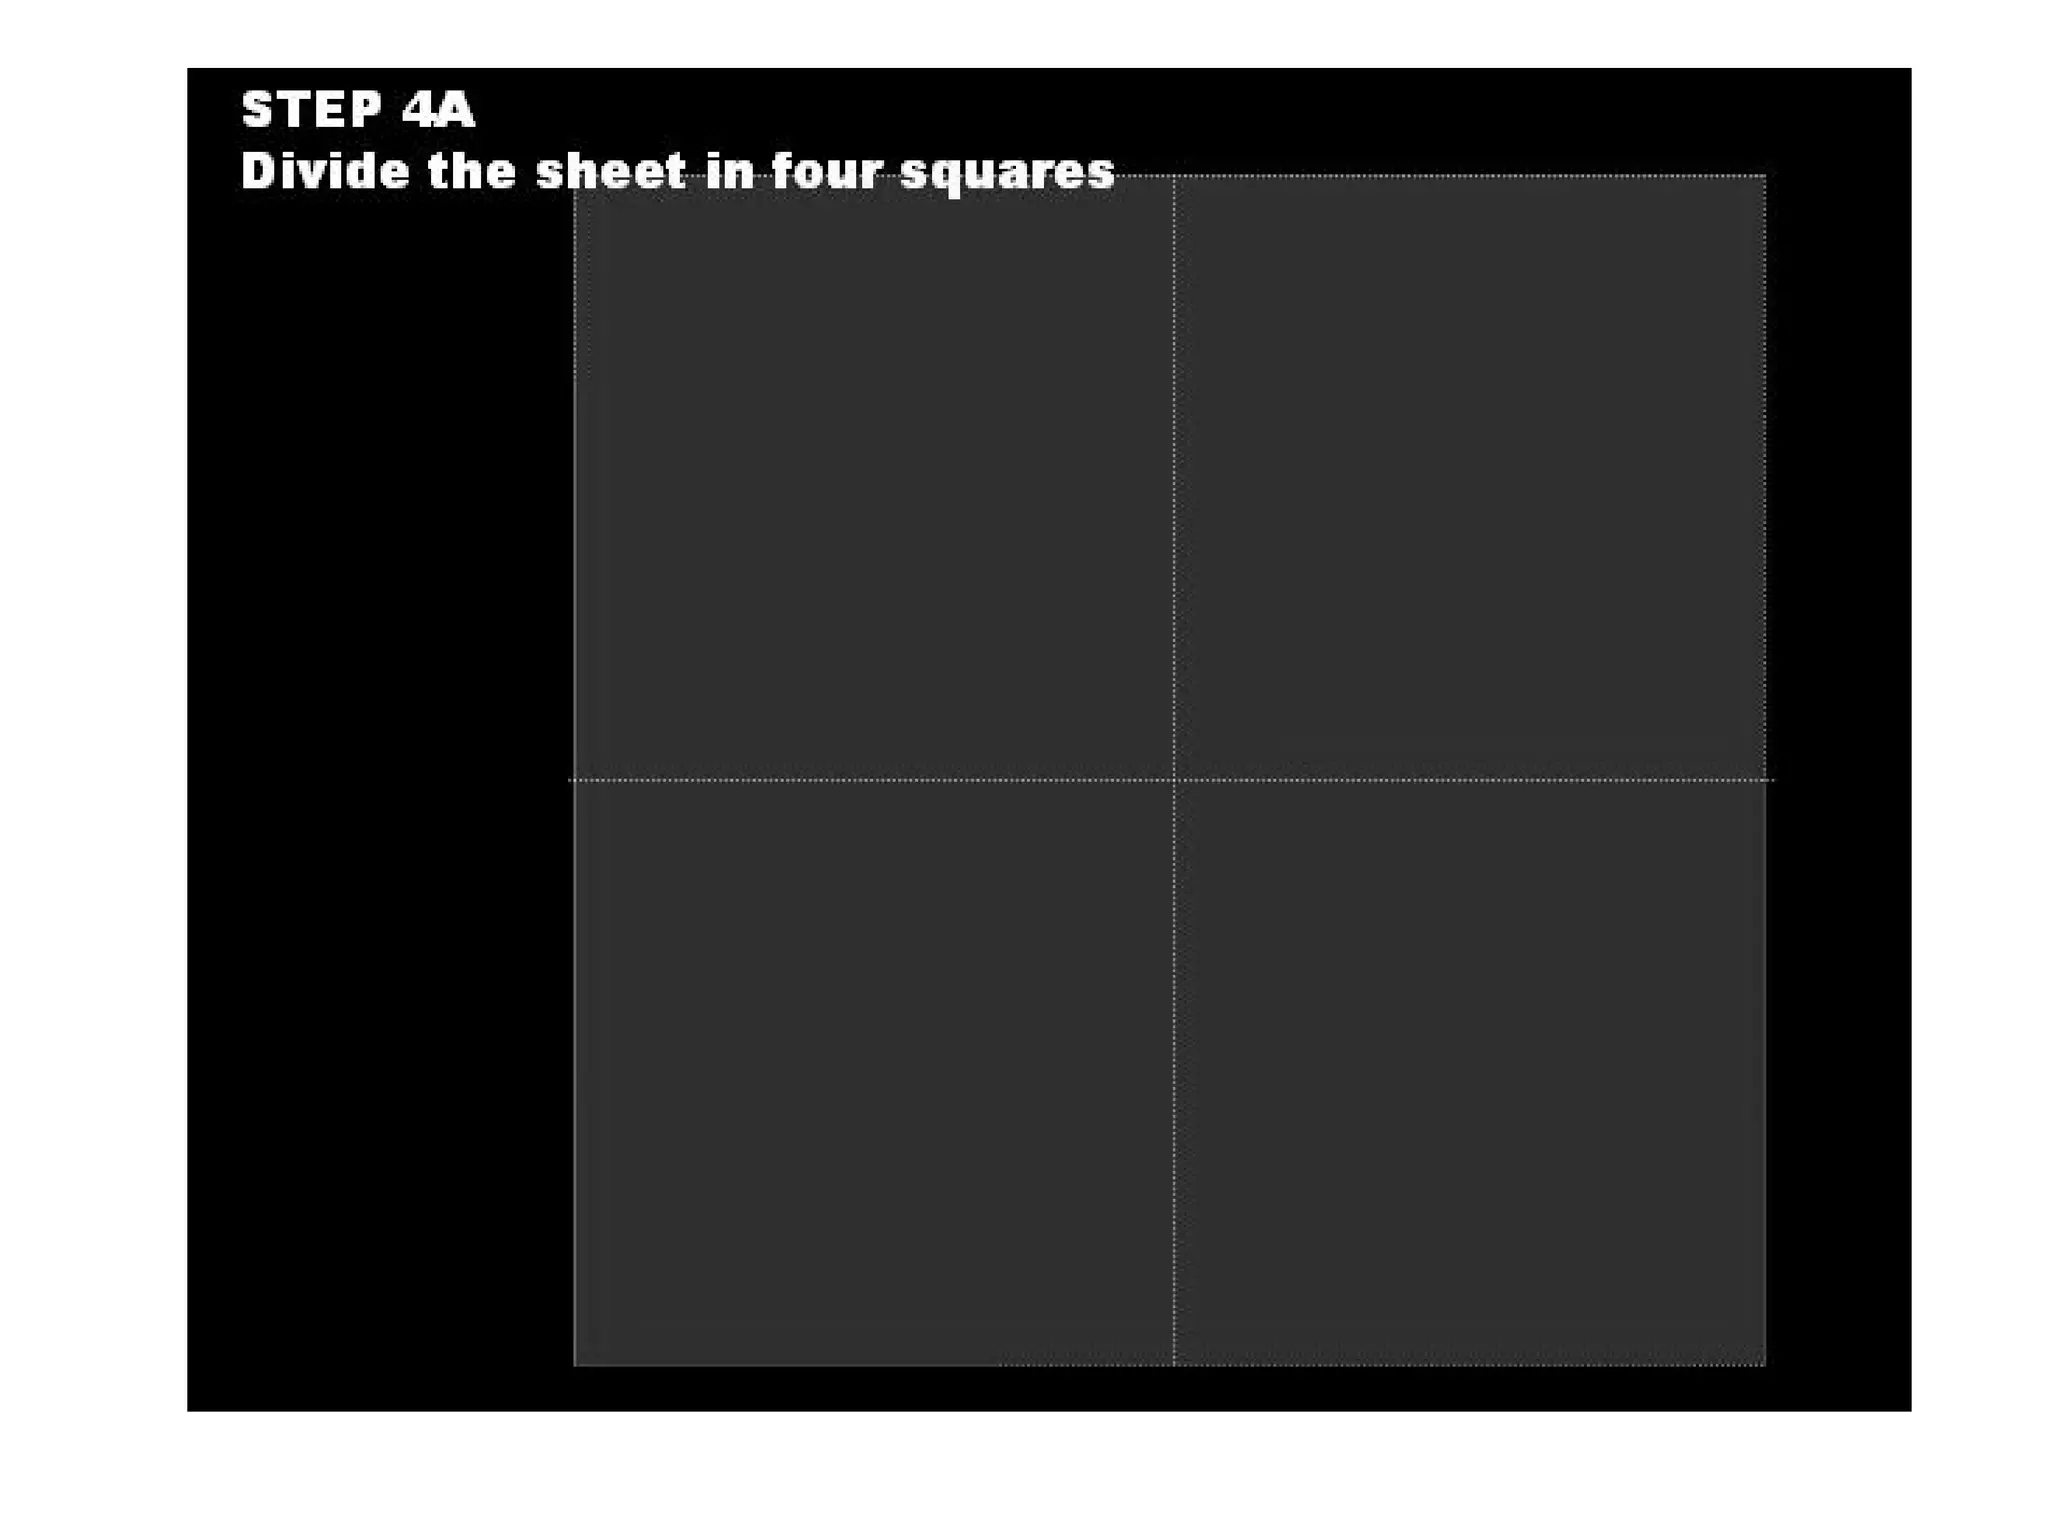

This document discusses the materials and components used for rubber dam isolation in dentistry. It describes the different types of rubber dam materials including color options and napkins to absorb moisture. It also outlines the tools needed such as punches to make holes, templates and stamps to guide hole placement, clamps to secure the dam, and other accessories like wedges and lubricant. Finally, it provides guidance on punching holes for different types of teeth and properly placing clamps in the rubber dam.